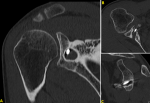

Case 1: X-rays showed osteolysis around proximal screw which was not bi-cortical. There was no geode around distal screw which was bi-cortical. There was no sign of omarthrosis (Figure 1). Computed tomography (CT) scan showed complete osteolysis of the coracoid bone block. Major geode was visible around proximal screw flush with glenoid articular surface communicating with joint through a thin opening. Volume of the bony defect was 8.3 cm3 (Figure 2).

Figure 1: (A,B) frontal and lateral X-rays of right shoulder showing a geode in scapular neck